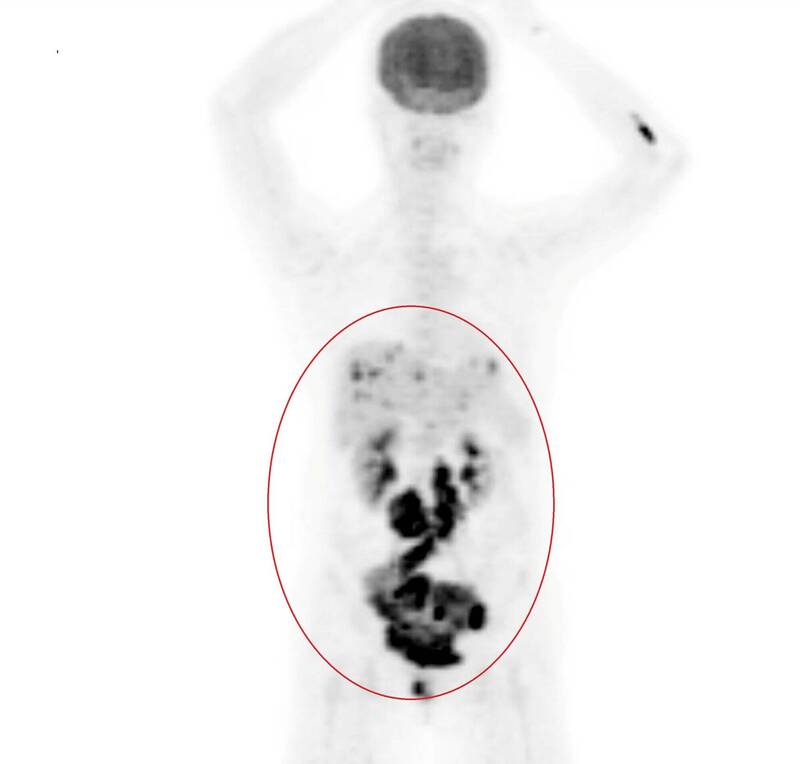

葛裕民指出,患者透過陰道超音波、子宮內膜切片或子宮鏡等詳細檢查,並以子宮內膜搔刮術在子宮內膜採樣後,確認是子宮內膜癌,正子影像檢查更發現有擴散到骨盆腔淋巴結、肝臟,確認為第4期,相較於早期診斷存活率,第1期患者5年存活率可達90%以上,晚期患者的5年存活率則明顯下降至20~50%不等。

為確認子宮內膜癌是否擴散,醫生必要時會安排正子攝影檢查。(記者陳建志翻攝)